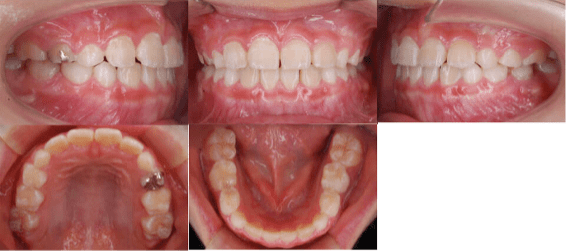

<治療前>

- 初診時年齢:7歳2ヶ月

- 主訴:前歯のかみ合わせが反対

- 診断:前歯部反対咬合

- 抜歯の有無:非抜歯

- 治療内容:マウスピース型カスタムメイド矯正歯科装置(製品名インビザライン 完成物薬機法対象外)を使用して主訴である前歯の交叉咬合を改善しました。

- 治療期間:6ヶ月 通院回数6回

- リスク:矯正歯科装置を付けた後しばらくは違和感、不快感、痛みなどが生じることがあります。

- 治療中は矯正歯科装置が歯の表面に付いているため食物が溜りやすく、また歯が磨きにくくなるため、むし歯や歯周病が生じるリスクが高まります。

- 歯を動かすことにより歯根が吸収して短くなることや歯肉がやせて下がることがあります。

- 費用:40万円